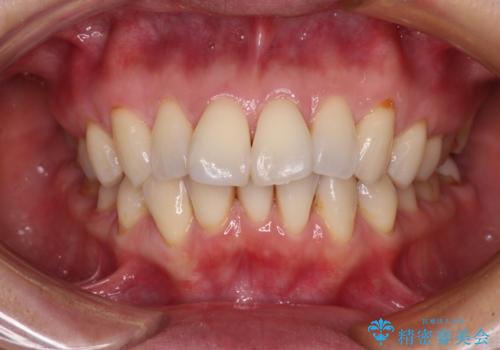

- 口元の突出感を改善したい。審美装置による抜歯矯正- 担当医 齋藤佑磨